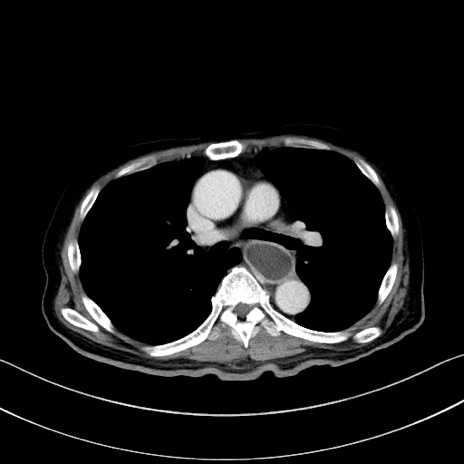

症例28(横断像)

【症例】60歳代男性

【主訴】嘔吐

【現病歴】胃癌にて胃全摘後。食思不振が悪化し、夜中に嘔吐することがある。

【既往歴】胃癌、胃全摘、脾摘、胆摘後

【データ】WBC 5900、CRP 10.56